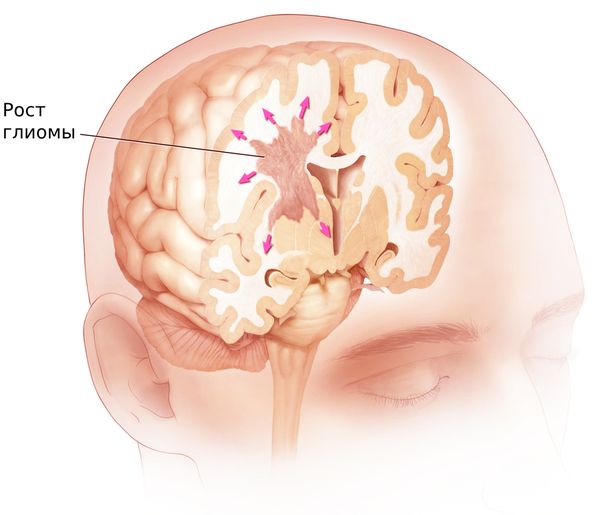

Хроническая ишемия головного мозга и лейкоареоз: симптомы и лечение